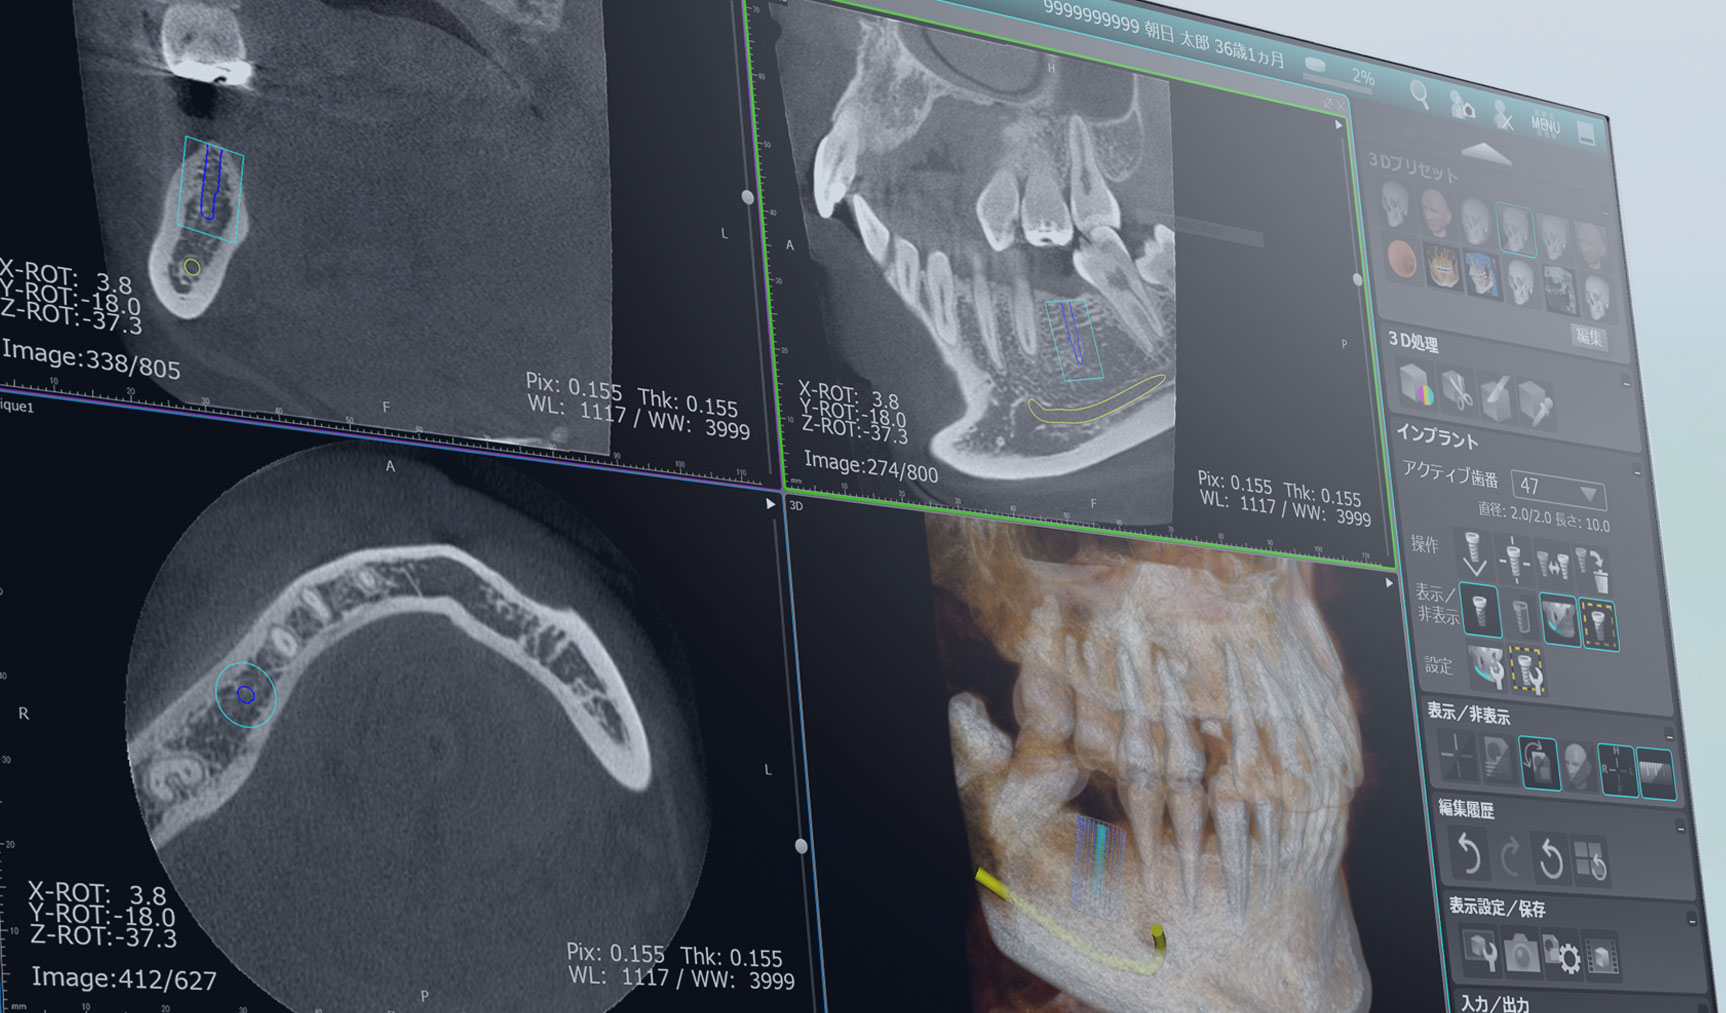

駒沢よしや矯正歯科では、より正確で安全な診断を行うために歯科用CT(コンビームCT)を導入しています。この技術により、従来のエックス線写真では得られない詳細な情報を確認し、患者さま一人ひとりに治療計画を立てることが可能です。

歯科用CT(コンビームCT)は、歯や顎骨、神経、血管などを三次元(3D)で映し出すことができる画像診断装置です。

- 親知らずの抜歯や埋伏歯の診断

- 顎関節症の診断

- 骨の成長や形態の詳細な確認

- インプラント治療を検討している場合

安心・安全な検査環境で、正確な診断と効果的な治療計画を。7 歯科用CT

歯科用CTで得られる情報

顎骨や歯の詳細な構造

骨の密度や形状、歯根の位置などを正確に把握します。

歯の埋伏や異常の確認

親知らずや埋伏歯の位置を詳しく診断します。

神経や血管の位置の確認

矯正治療や外科処置において、神経や血管を傷つけないよう計画を立てます。

病変や異常の発見

顎の中に隠れた病変や異常を早期に発見することが可能です。

歯科用CTのメリット

診断の精度向上

平面のエックス線写真では見えなかった部分も3D画像で確認できるため、診断の精度が格段に向上します。

治療の安全性を確保

歯や顎骨の状態を立体的に把握することで、安全かつ効果的な治療が可能です。

患者さまへのわかりやすい説明

3D画像を使って治療計画を説明するため、患者さまも自身の状態をより理解しやすくなります。

駒沢よしや矯正歯科の歯科用CT

当院では、歯科用CT機器を使用して、放射線量を最小限に抑えた安全な撮影を心がけています。短時間で撮影が完了するため、患者さまの負担も軽減されます。

歯科用CTが必要なケース

安心して治療を受けられるために

駒沢よしや矯正歯科では、歯科用CTを活用して精密な診断と治療計画を提供しています。